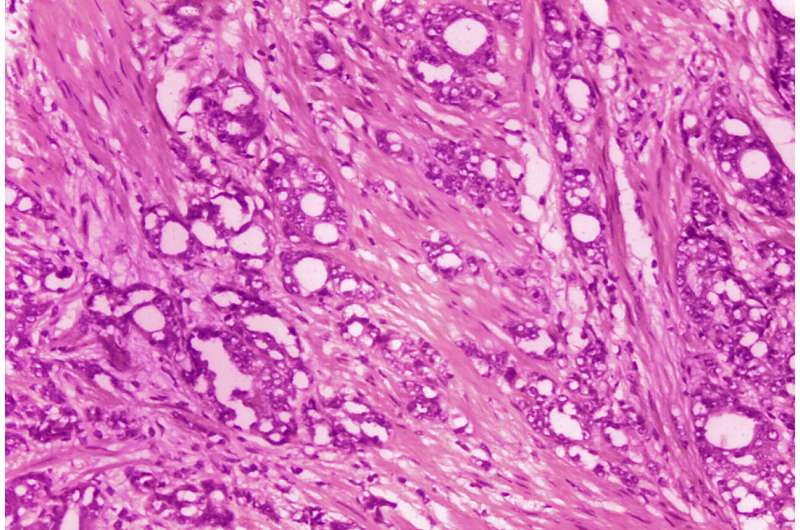

当病人有可疑的检测结果时,医生可能会建议进行活检,即从前列腺中提取组织样本。接下来,病理学家在显微镜下观察,并对样本的细胞异常程度打分。

通常,医生会给病人最低的格里森(Gleason)6分——一种避免手术和放疗的方法:主动监测,包括密切监测,但不立即治疗。